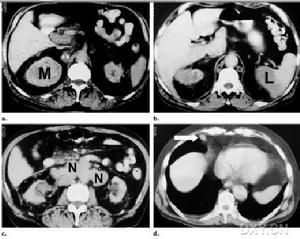

3.CT表現:平掃可見腎局部隆起,內部密度不均勻偏低,其內可見斑片或小點狀鈣化,有時呈蛋殼狀;增強掃描後正常部分腎增強明顯,而癌內增強較低,內部增強程度不規則,有更低密度的壞死區存在。癌可穿破包膜進入腎周脂肪層,晚期穿破腎筋膜擴散至腎外組織。腎細胞癌分期多採用Robson分期法,即Ⅰ期癌限於腎包膜內;Ⅱ期癌已穿破包膜,侵入脂肪層,仍局限在腎筋膜內;Ⅲ期癌已侵入腎靜脈或(和)下腔靜脈,局部淋巴結可能有轉移;Ⅳ期癌已穿破腎筋膜,侵入鄰近臟器或發生遠處轉移。

4.MR表現:在多體位觀察了解腫瘤侵犯範圍,略勝CT一籌。